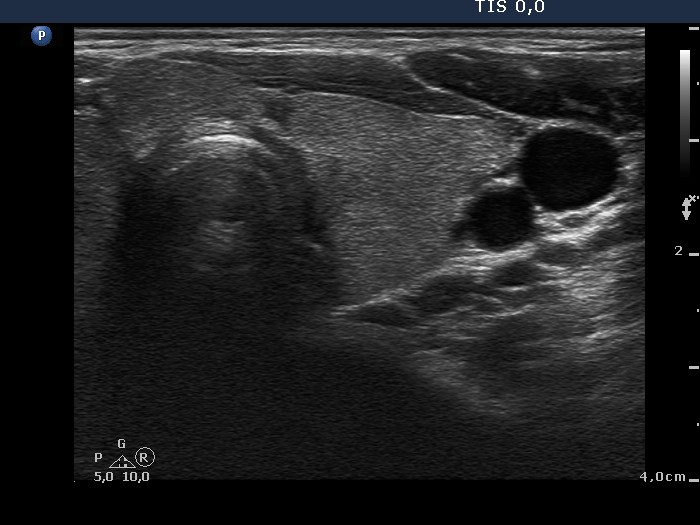

Follow-up investigation 40 months after first visit (ultrasonographic picture 4)

Patient on daily 5 mg methimazole therapy in hypothyroid state

Left lobe, transverse view. The thyroid is intact.